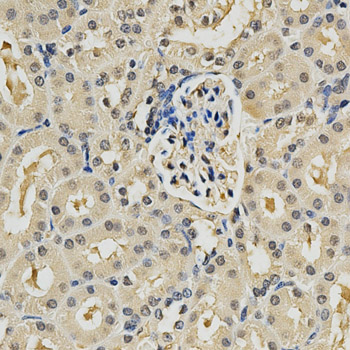

Immunohistochemistry of paraffin-embedded mouse kidney using PSMB9 antibody at dilution of 1:200 (x400 lens).